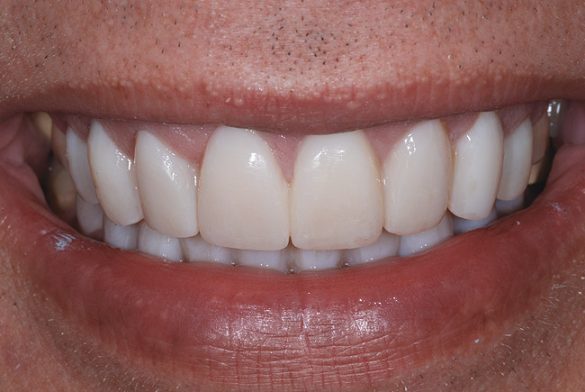

Fotografiile finale ale acestui caz au pus în evidenţă genul de rezultate care se pot obţine urmând sistemele şi tehnicile dovedite (fig. 8-11). S-au realizat obiectivele de îmbunătăţire a raportului “alb-roz” alături de cele legate de zâmbetul pacientului. Perceperea în mod clar a obiectivelor acestui caz şi capacitatea de a comunica cu acurateţe cu pacientul şi ceramistul reprezintă o parte din cheia succesului.

Utilizarea camerelor digitale şi a tehnologiei de amprentare digitală permite durate de livrare mai scurte şi eficientizate, cu îmbunătăţirea abilităţii de comunicare. Acest caz este un exemplu al modului în care planificarea şi comunicarea adecvată produce rezultate sporite, rezultate clinice excelente şi o estetică funcţională îmbunătăţită.20 La momentul publicării, pacientul se afla la şedinţa de evaluare după un an, fără nicio problemă raportată sau diagnosticată.